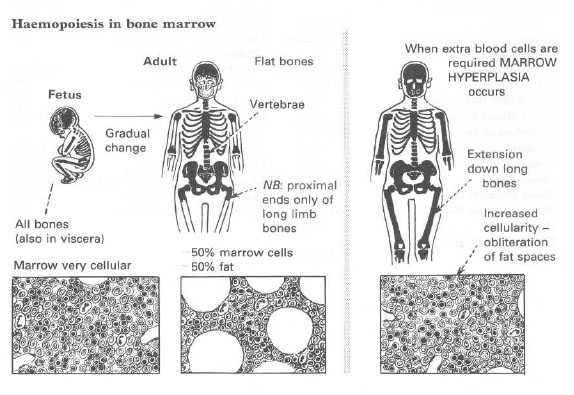

Fiziopatologia seriei rosii

Fiziopatologia seriei rosii Hematopoeza Eritropoeza ANEMIILECiteste tot ... 1861 cuvinte

Dimensiune medie

+ cu poze |